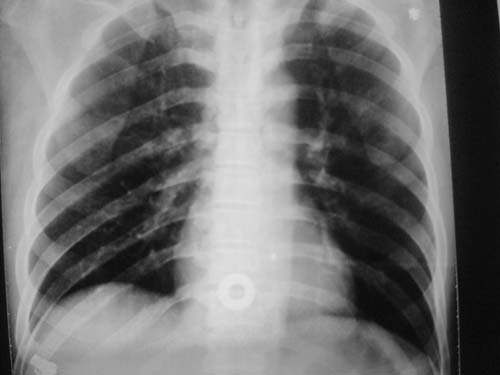

这是第三天拍的片子.

支持肺水肿,双侧胸腔积液,入院第三天发病,会不会是心源性、药物过敏性、快速输液等情况,建议提供病史。

支持肺水肿,双侧胸腔积液.

入院第三天发病,会不会是心源性、药物过敏性、快速输液,栓塞,ards等情况,建议提供病史及患者转归情况。

患者第三天后逐渐加重,不符合肺挫伤表现,因为肺挫伤大部分是以外伤后24小时或36小时为发病高峰,之后就开始吸收。

不知道具体外伤的情况(部位,方式‘程度等),肺内病变范围较广,上下叶都有,似乎与肺挫伤不相符合,是应该看看临床治疗详情,特别是输液出入量,以前见过类似的病人,间质性肺水肿可能大!等待结果,盼盼盼!

1)双侧创伤性湿肺。2)双侧胸腔积液。

跟主治医生讨论病例

结果:病人刚入院水电解质紊乱,治疗期间大量输液,而且速度较快,正如4.5楼那样说的引起肺水肿,对症治疗后病情好转,